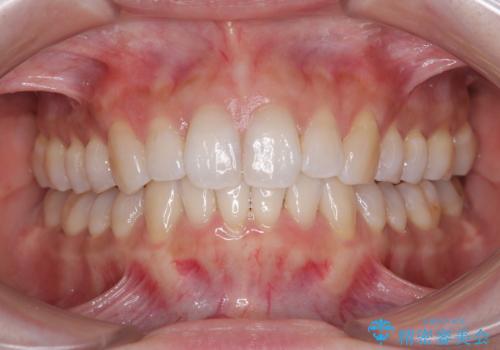

【非抜歯】インビザラインで正しい噛み合わせを

【非抜歯】インビザラインでガタつきと口元を改善!非抜歯でも印象が変わる矯正治療